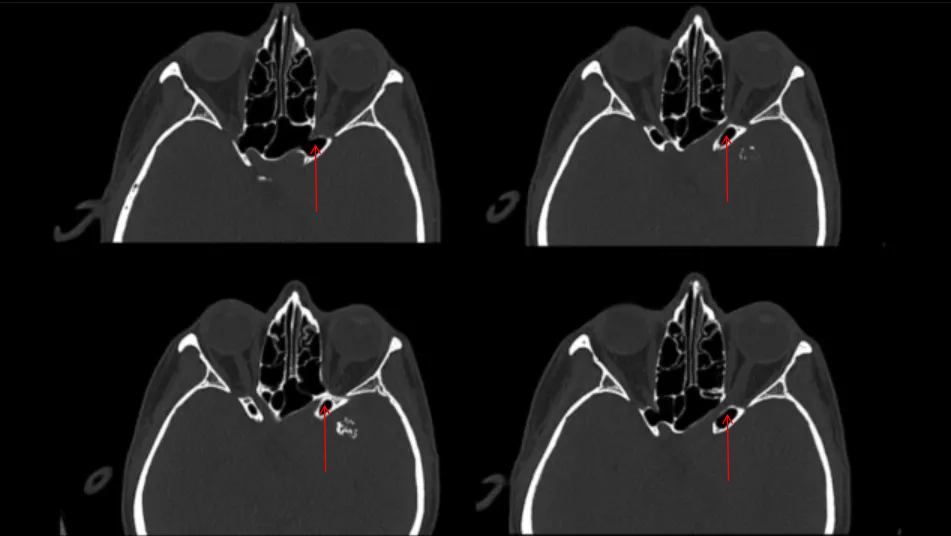

▼本例特殊之处在于骨窗CT显示前床突气化。正常情况下,前床突是实心的,前床突气化术后有脑脊液漏的风险,所以颅底修补至关重要。

识别并磨除前床突;磨除时仔细分辨气化部分,电凝蝶窦黏膜,避免穿破。